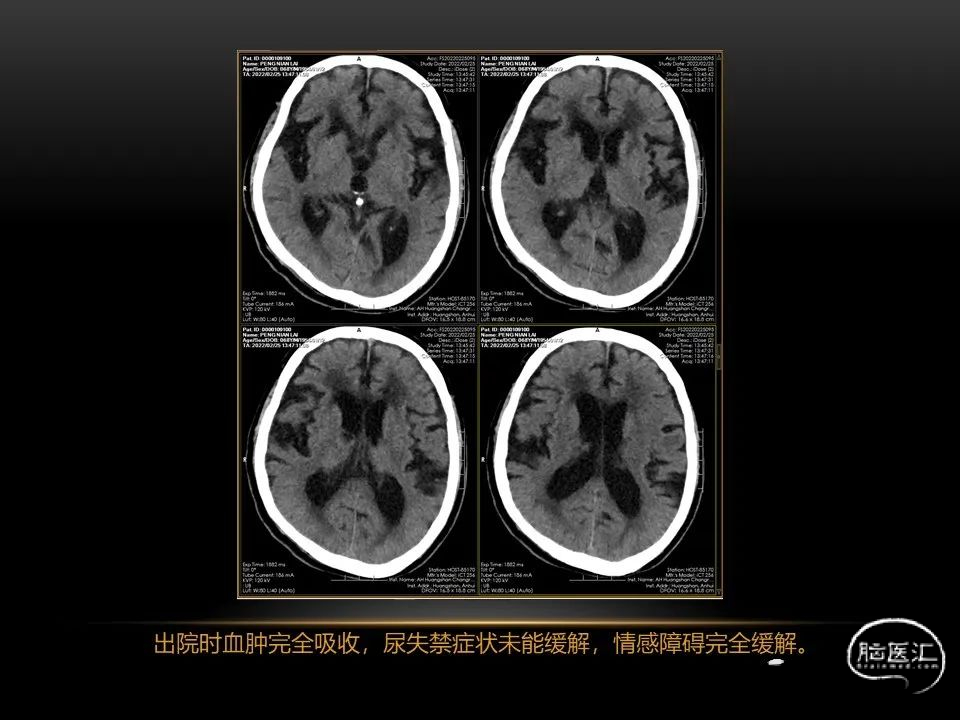

自发性脑出血临床上很常见,不同原因有特征性的出血部位。例如:基底节出血和丘脑出血大多是高血压性脑出血;脑叶出血,特别是多次复发的脑叶出血多见于老年人的脑血管淀粉样变。

自发性脑出血不仅仅累及内囊后肢才会出现偏瘫及偏身感觉障碍,病变累及大脑脚或辐射冠同样有可能有类似症状和体征。内囊、辐射冠、大脑脚等结构之间是延续的,只是不同区域不同名称而已。定位诊断需要对解剖结构概念清晰,读片准确辨认,灵活掌握。